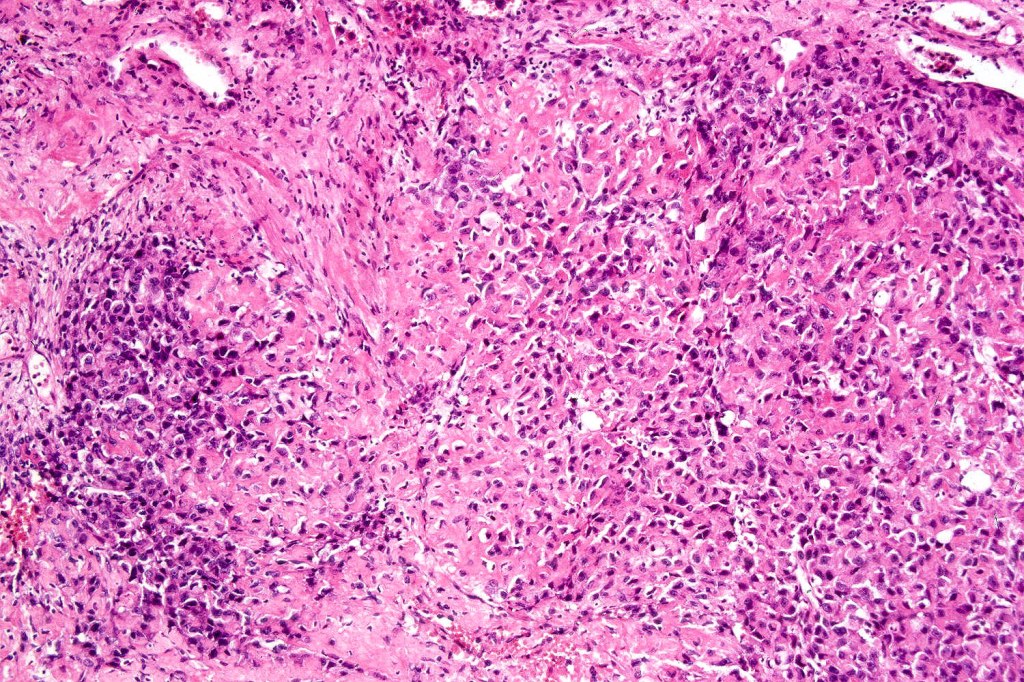

Melanoma with osteoid and chondroid (benign or malignant) are most often encountered in the digits particularly the thumb and large toe, for the other types, they are too rare to make any meaningful clinical comments. Documented heterologous elements include:

•Smooth muscle fibroblastic/myofibroblastic

•Rhabdomyosarcomatous